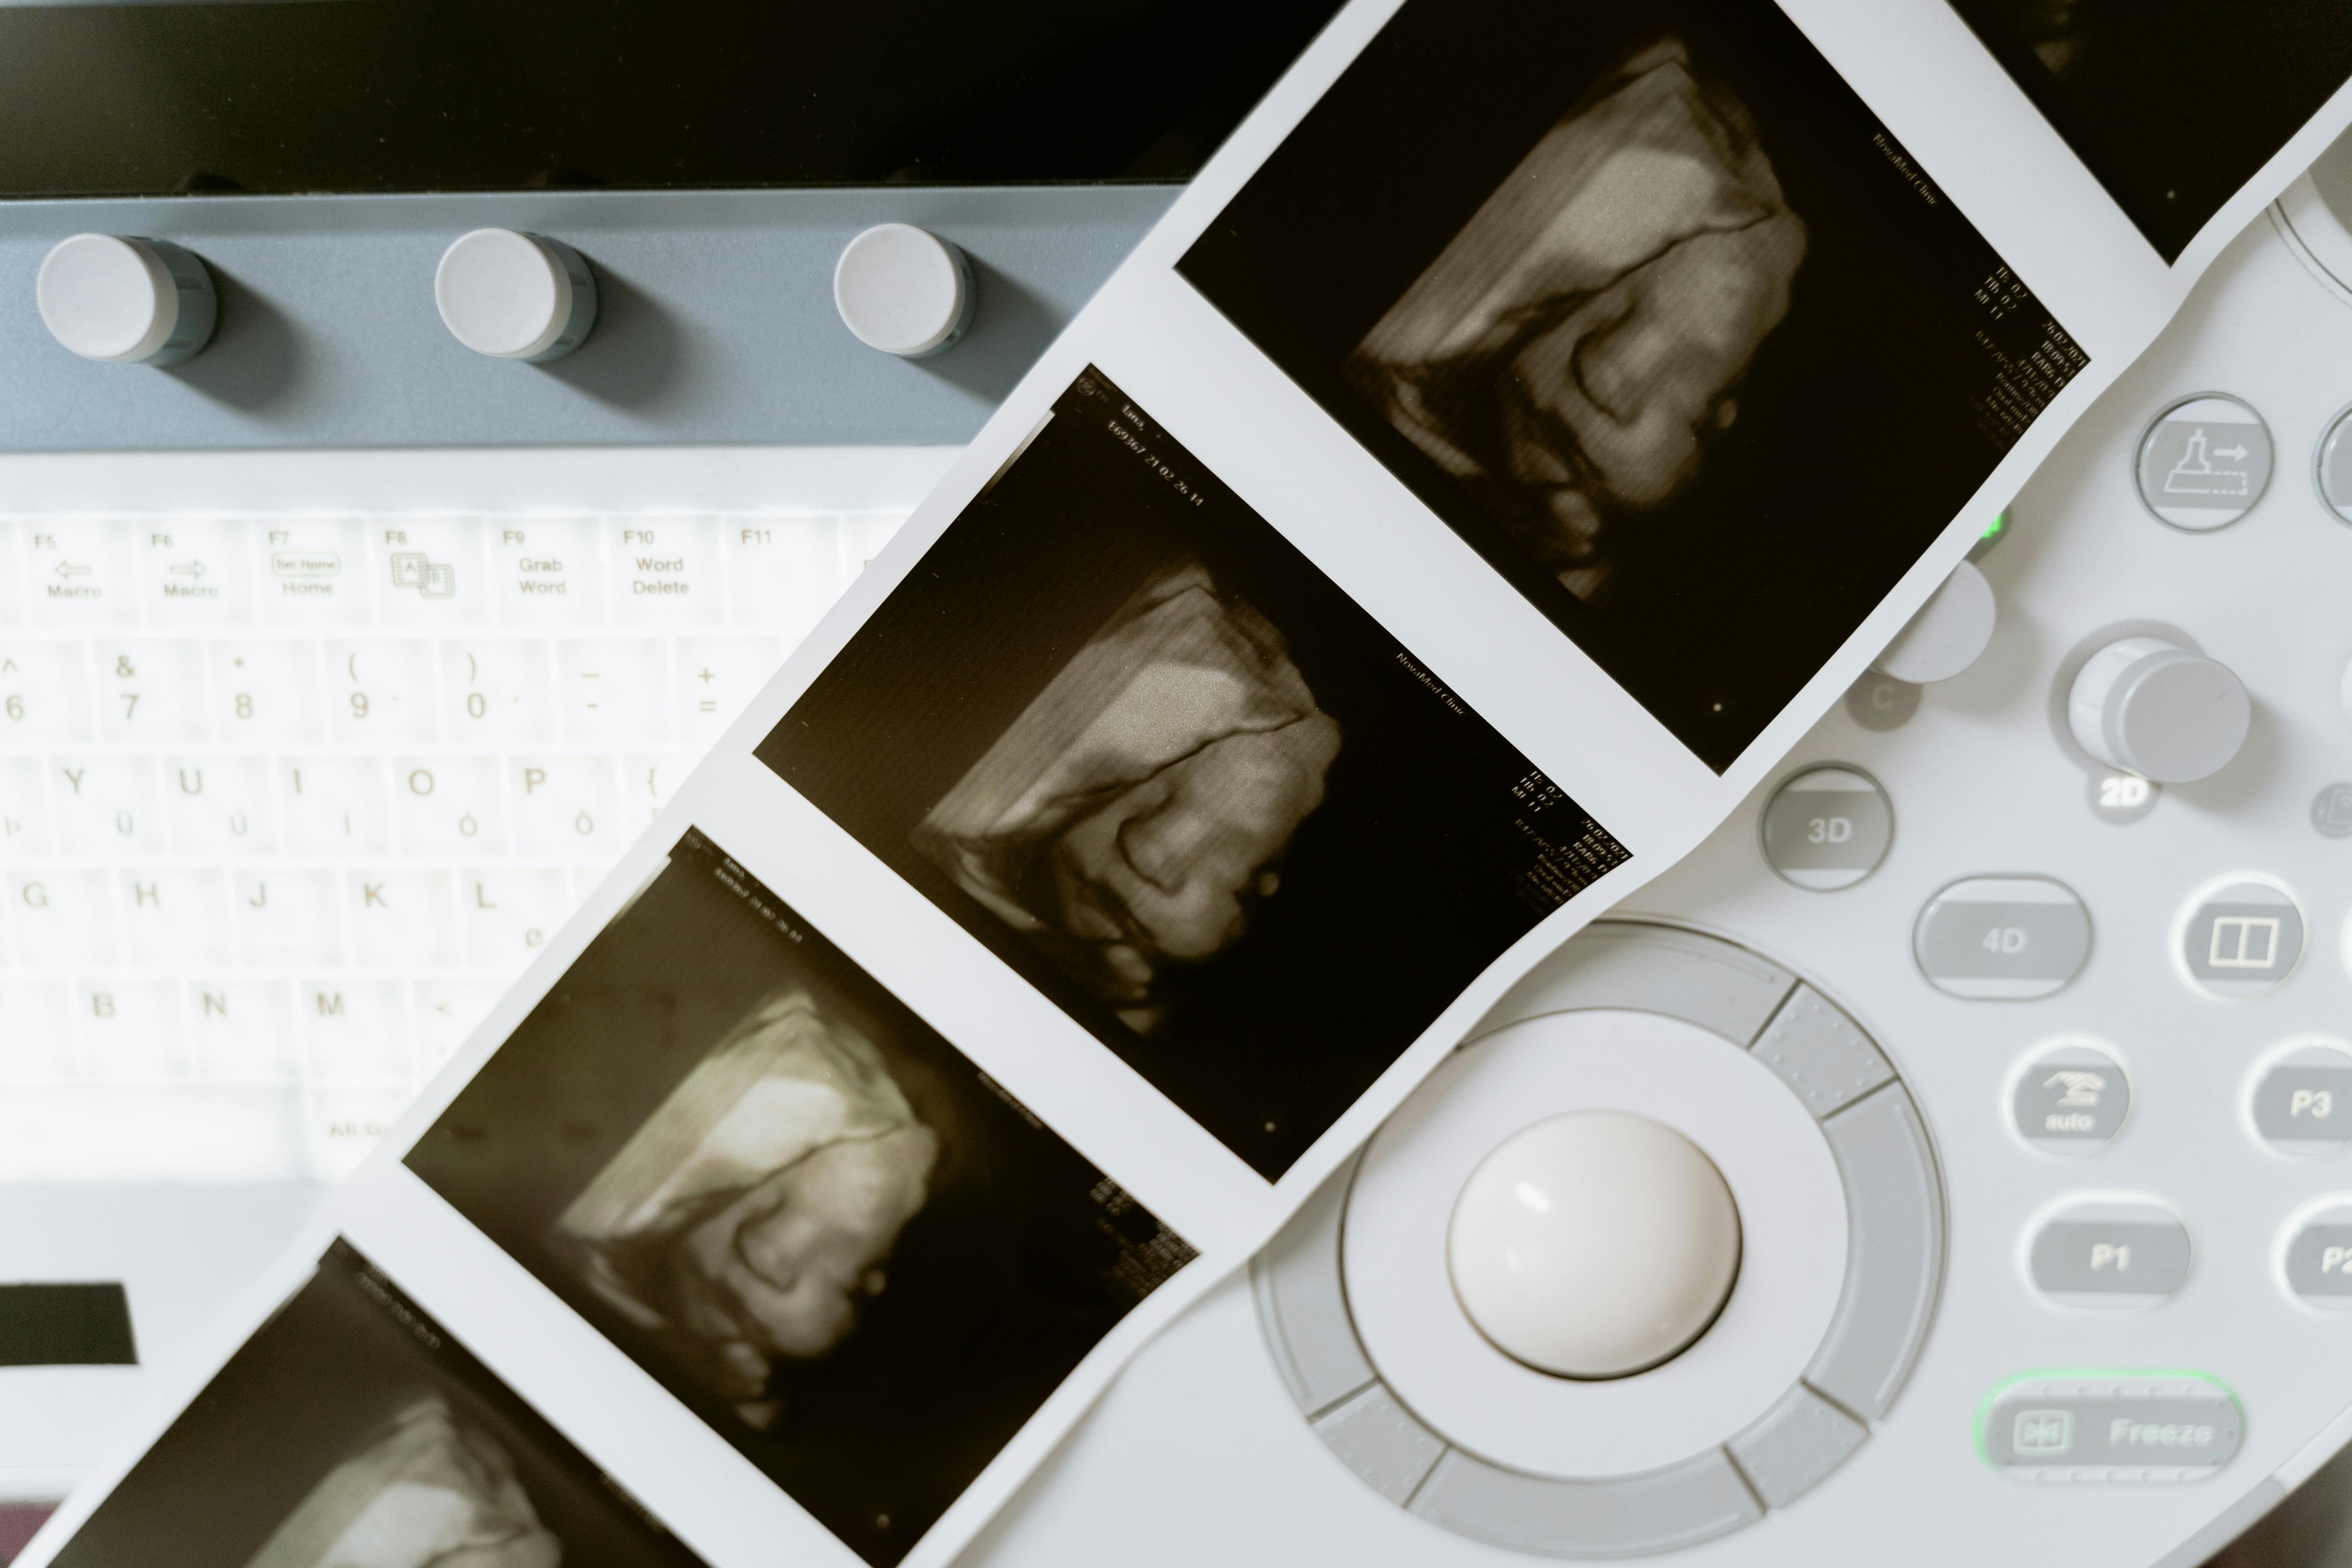

Ultrasound Scan

An ultrasound scan (or sonogram) is a procedure that uses high-frequency sound waves to create an image of inside the body.

It is commonly used to monitor a foetus, investigate symptoms further or diagnose a condition.

Depending on how far along your pregnancy is, ultrasound images help your doctor:

– Estimate your due date

– See the position of the placenta

– See the size, position, movement, breathing and heart rate of the fetus

– See the amount of amniotic fluid in your uterus

– Find multiple pregnancies (twins, triplets, etc).